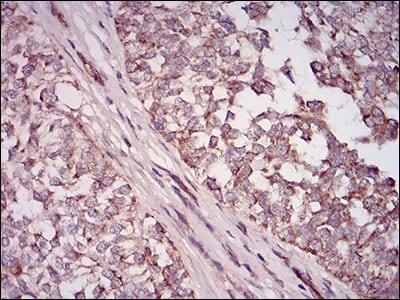

分类: 科研抗体货号: 30611别名: NT; eN; NT5; NTE; eNT; CD73; E5NT; CALJA应用: WB,IHC反应种属: Human